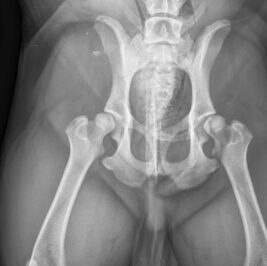

Artemis har digitalt røntgenudstyr. Dette betyder at røntgenbillederne kommer digitalt frem på en computerskærm og nemt kan viderebringes til ejer eller kollegaer. Digital røntgen har den fordel at billedkvaliteten kan opjusteres efter optagelsen, og dermed fremmes diagnosticering ud fra røntgenbillederne.

Den gode billedkvalitet er en fordel, hvis dyret er uroligt under en optagelse, da antallet af optagelser minimeres, og dyret dermed hurtigst muligt kommer ned fra røntgenbordet.

Artemis har godkendte dyrlæger til at tage røntgenbilleder af hofter og albuer til Dansk Kennel Klub (DKK). Dyrlægen skal have en særlig autorisation for at må optage disse billeder. Skal dyret fotograferes til DKK skal dyret bedøves. Bedøvelse er et krav fra Dansk Kennel Klub og er med til at sikre de mest optimale optagelser af dyrene. Se mere hos www.dansk-kennel-klub.dk.